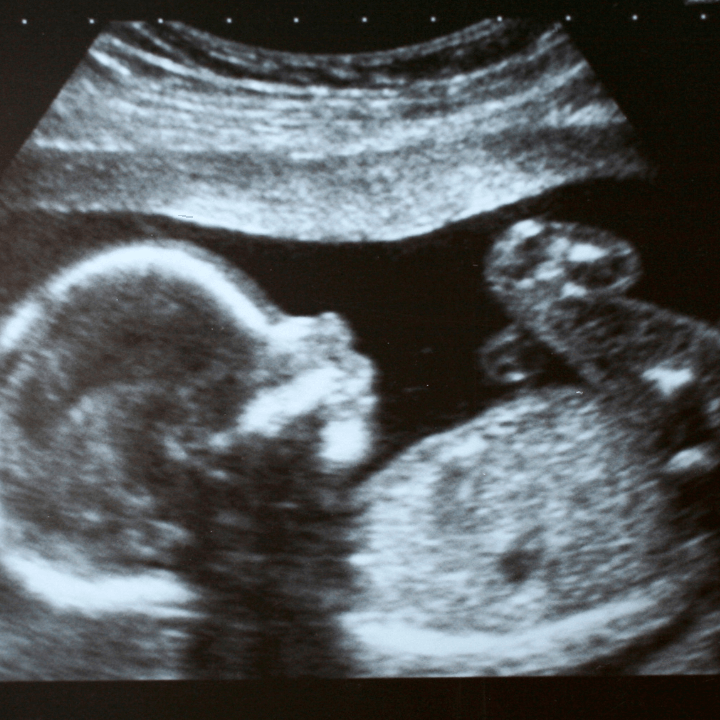

O que é o Ultrassom Morfológico?

O Ultrassom Morfológico é um exame essencial entre a 20ª e 24ª semana de gestação. Ele avalia com riqueza de detalhes a formação do bebê, identificando possíveis alterações anatômicas e garantindo mais segurança para a mamãe e o obstetra.

✅ Avaliação completa da anatomia fetal

Visualização detalhada do bebê em formação

✅ Alta resolução de imagem

Mais nitidez para diagnósticos precisos